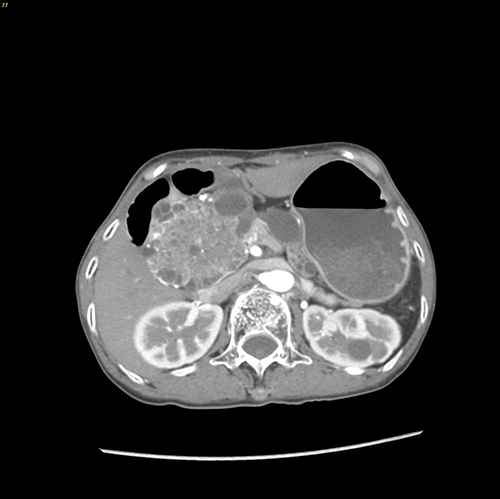

胰头囊腺瘤---胰十二指肠切除